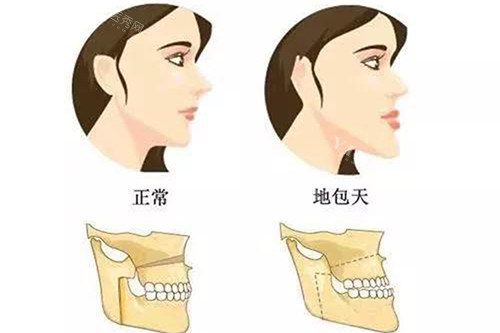

六、地包天矫正:价格因复杂程度而异

价格:20000元-50000元起

特点:地包天(反颌)矫正需结合骨性或牙性程度,轻度牙性地包天可用传统牙套矫正,费用约20000元;重度骨性地包天需正畸+正颌手术,费用可能超过50000元。